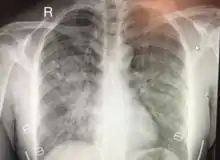

| Chest x-ray of HAPE showing characteristic patchy alveolar infiltrates with right middle lobe predominance. | |

Hypoxic pulmonary vasoconstriction (HPV) occurs diffusely, leading to arterial vasoconstriction in all areas of the lung. This is evidenced by the appearance of "diffuse," "fluffy," and "patchy" infiltrates described on imaging studies of climbers with known HAPE.[8]

On physical exam, increased breathing rates, increased heart rates, and a low-grade fever 38.5o C (101.3o F) are common.[8][3] Listening to the lungs may reveal crackles in one or both lungs, often starting in the right middle lobe.[8][3] Imaging studies such as X-ray and CT imaging of the chest may reveal thoracic infiltrates that can be seen as opaque patches.[13][8][3] One distinct feature of HAPE is that pulse oximetry saturation levels (SpO2) are often decreased from what would be expected for the altitude. People typically do not appear as ill as SpO2 and chest X-ray films would suggest.[8][3] Giving extra oxygen rapidly improves symptoms and SpO2 values; in the setting of infiltrative changes on chest X-ray, this is nearly pathognomonic for HAPE.[3]

Severity

The severity of HAPE is graded. The grades of mild, moderate, or severe HAPE are assigned based upon symptoms, clinical signs, and chest x-ray results for individuals.[7] The symptoms that are taken in to account while evaluation the severity of HAPE are difficulty breathing while exerting or while at rest, the presence of a cough and the quality of that cough, and the level of fatigue of the patient. On physical exam of a suspected HAPE patient the exam findings used to grade the severity are the heart rate, respiratory rate, signs of cyanosis, and severity of lung sounds.[7] Both symptoms and signs on physical exam can be used to evaluate a patient in the field. Chest X-rays are also used to evaluate the severity of HAPE when they are available.